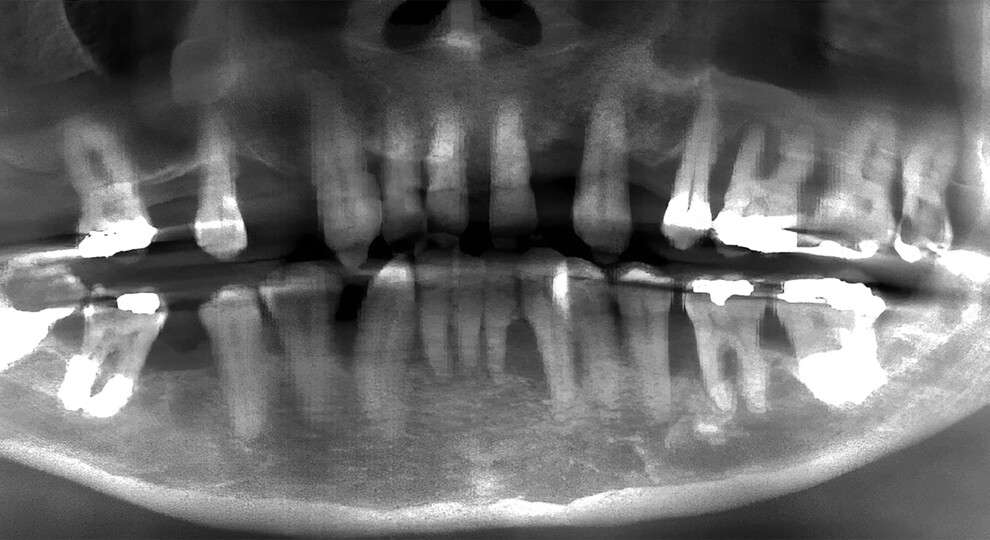

Fig. 2a: Pre-op panoramic radiograph showing extensive bone loss.

A 49-year-old male patient presented with failing maxillary and mandibular teeth. The findings of the clinical and radiographic examinations were severe periodontal disease, generalised bone loss, anterior spacing and tooth mobility, in addition to overall poor hygiene maintenance (Figs. 1a & b & 2a). The patient was informed of the findings, and several treatment options were discussed, including complete and/or partial dentures, implant-supported overdentures and implant-supported fixed restorations. After discussion regarding the options, the patient decided on full-arch implant-supported fixed restorations.